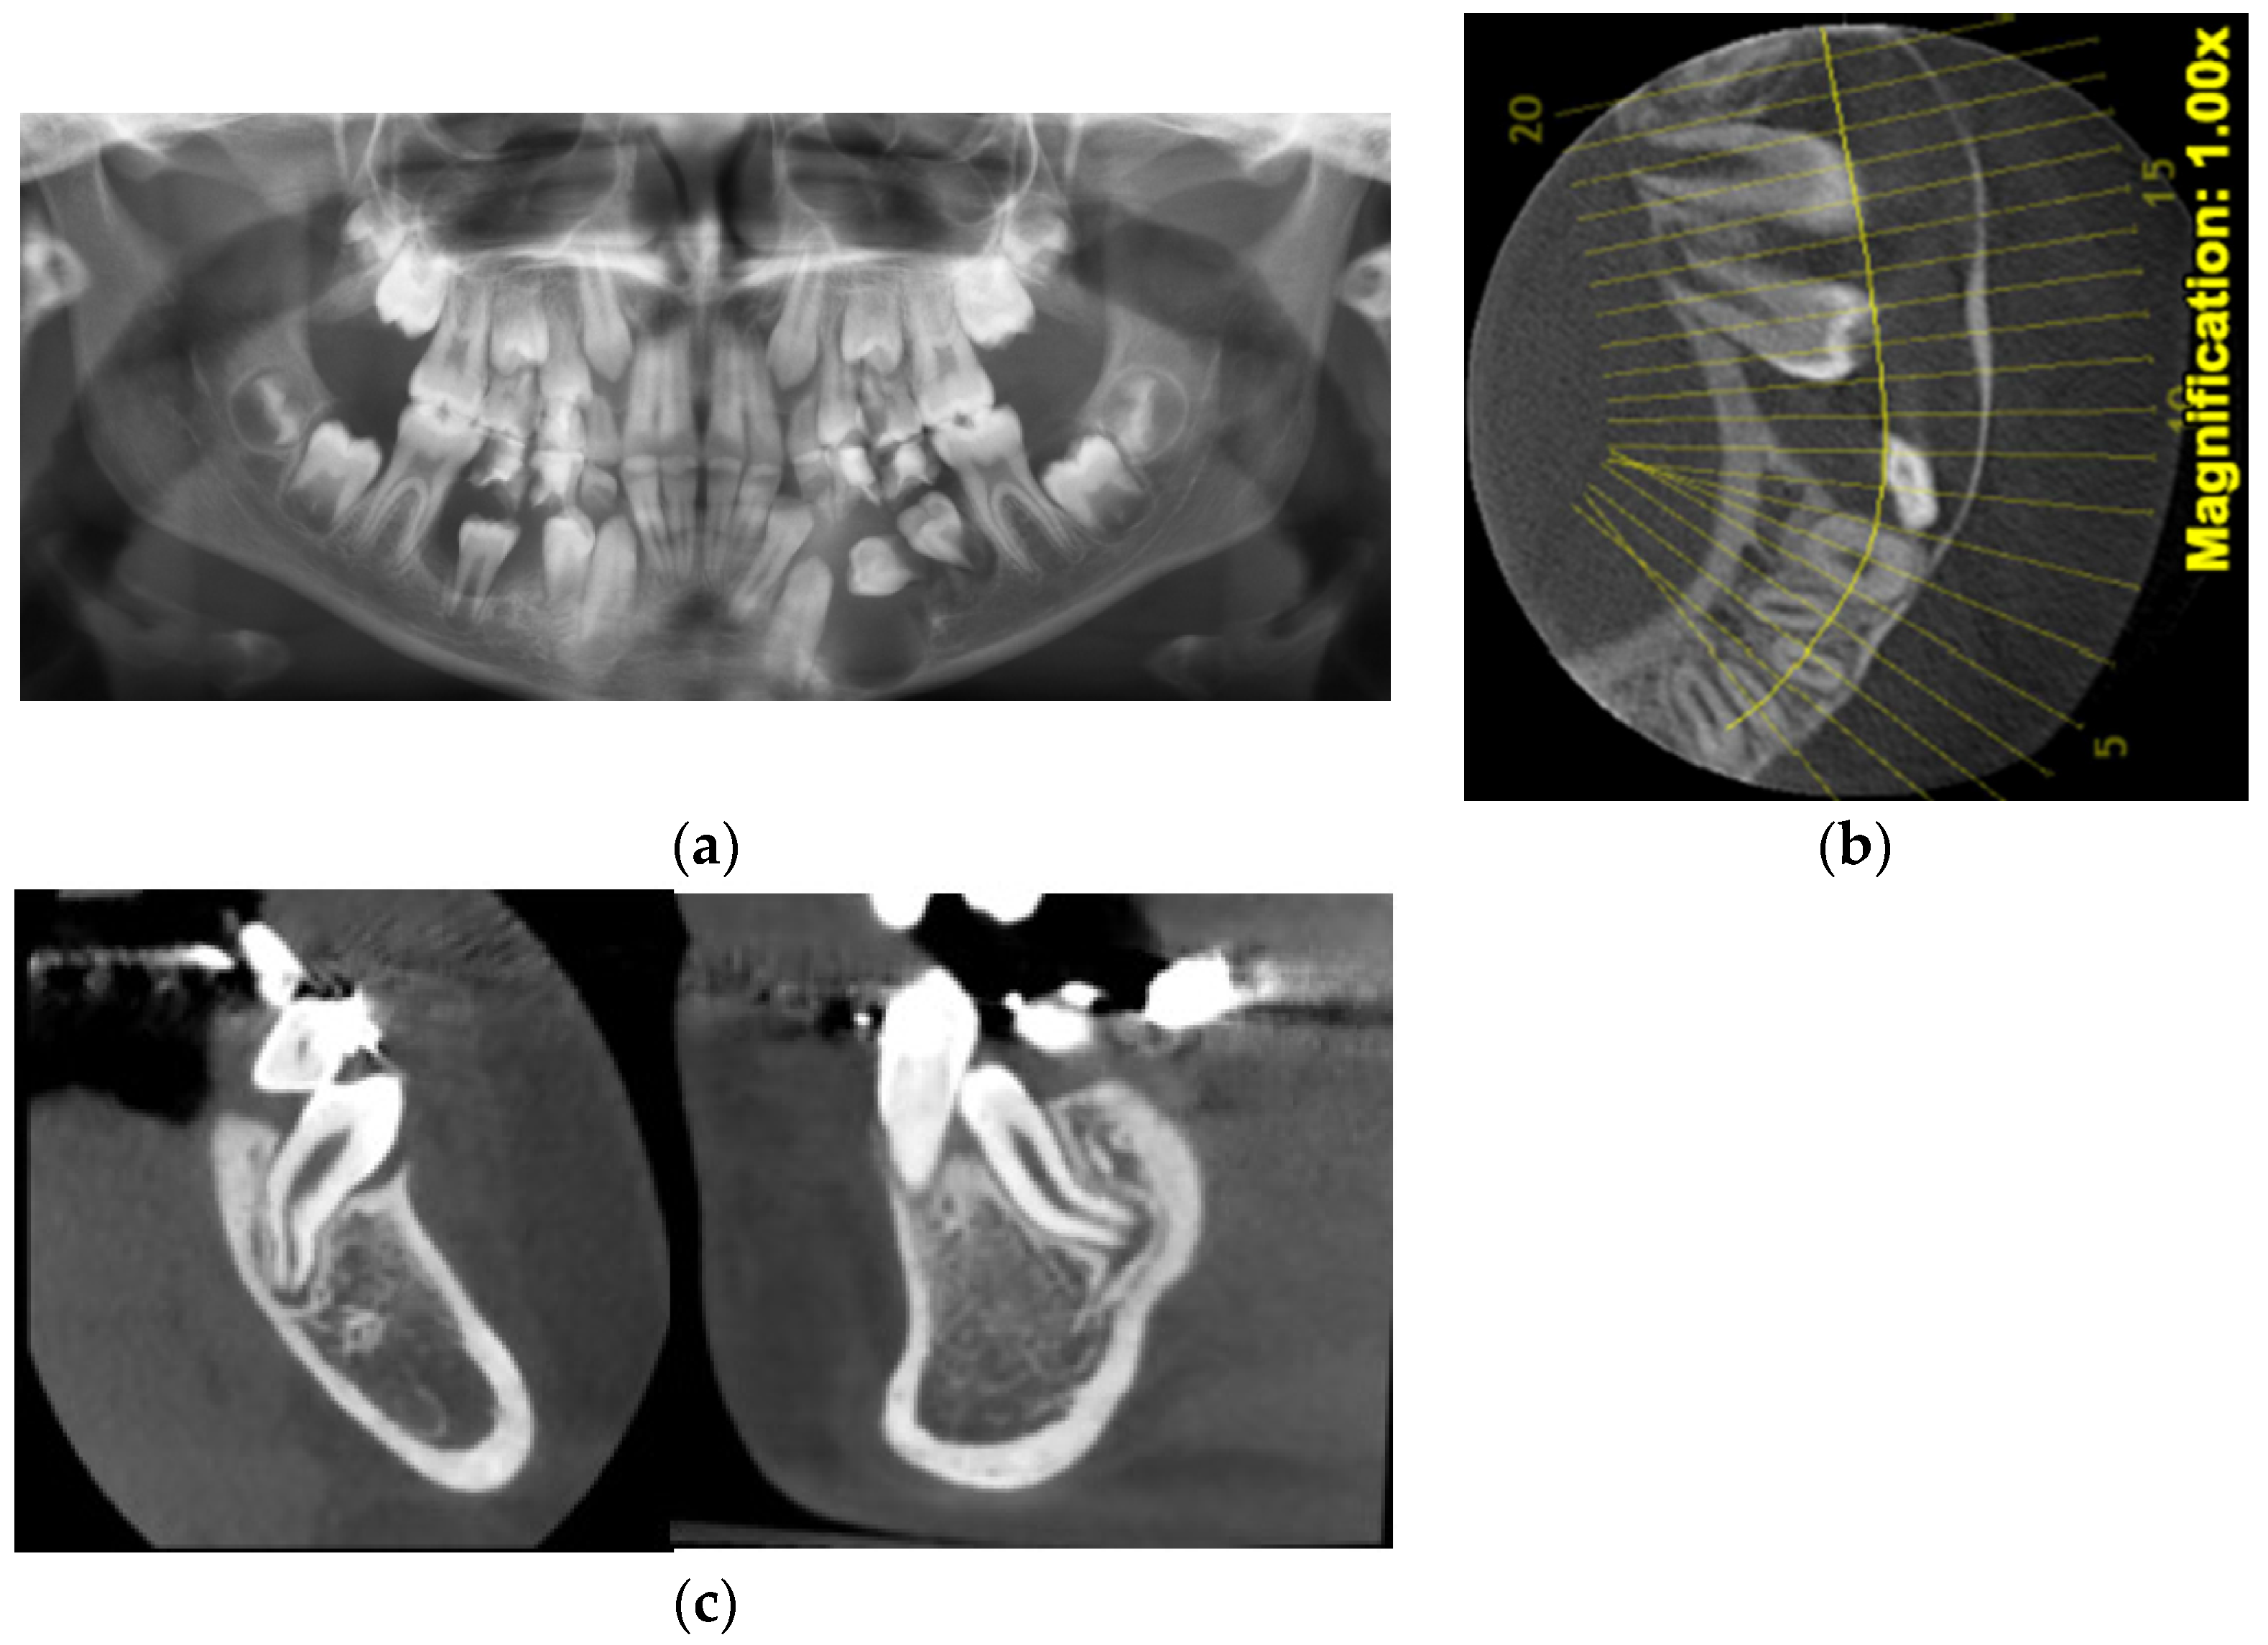

| Case Number | Summary of X-ray Findings |

| Case 3 |

|